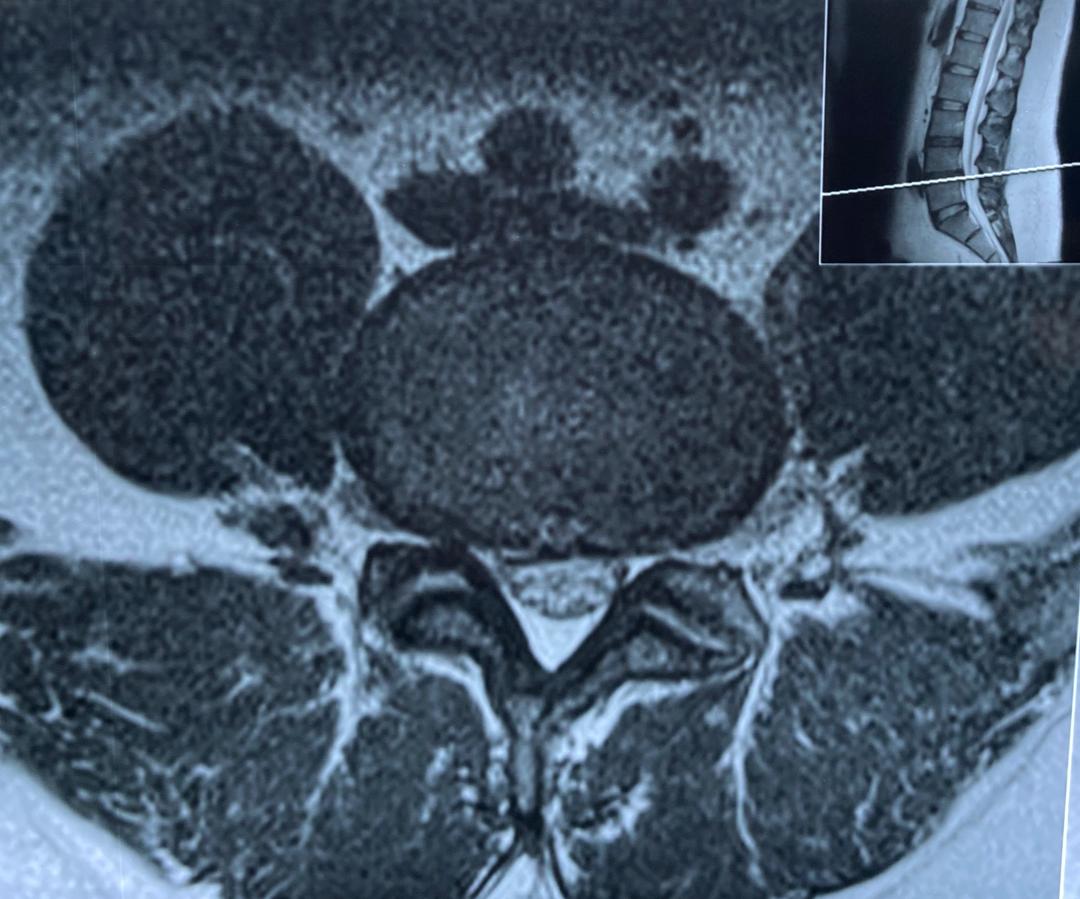

بیمار آقای میانسال با وزن ۱۳۰ کیلوگرم و درد بسیار شدید و مقاوم کمر و پای راست مراجعه کرده بودند.

تصاویر ام ار ای دیسک کمر